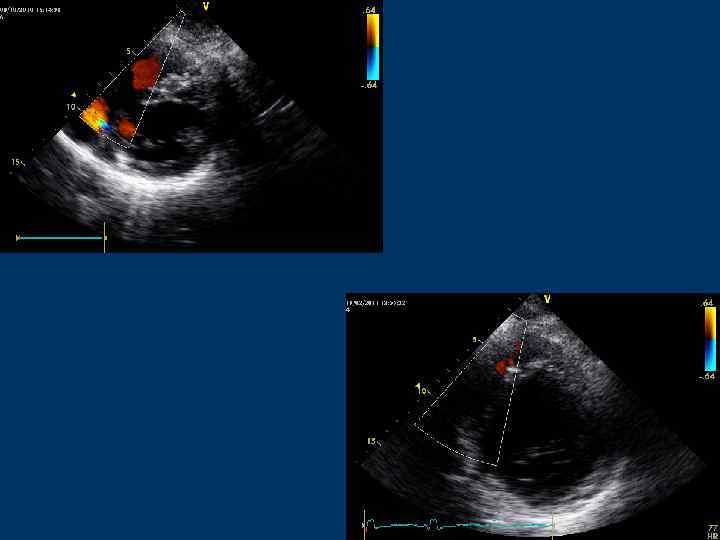

Трансмитральный диастолический поток Позиции: – Парастернальная позиция по длинной оси ЛЖ – Апикальная 4 -камерная – Апикальная 5 -камерная – Апикальная 2 -камерная – Апикальная 3 -камерная – Субксифоидальная

Трансмитральный кровоток

Трансмитральный поток

Трансмитральный диастолический поток Контрольный объем располагают в ЛЖ на уровне концов створок МК или в области фиброзного АВ кольца

Трансмитральный диастолический поток Скорость пика Е – 0, 9 м/с (0, 6 -1, 3) Скорость, пика А – 0, 2 -0, 4 м/с Е/А = 1, 6 -1, 7 (до 2)